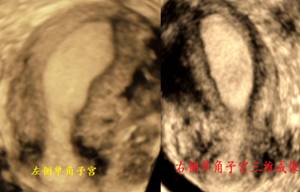

三、单角子宫(残角子宫)

二维超声纵切面上,乍看与正常子宫无差异。但是当连续移行扫查时发现子宫内膜只向一侧宫角延伸,另一侧宫角无内膜显示。宫旁侧常见一小团与宫体等回声的组织,即残角子宫,且与宫体之间有血流相连。由于残角组织内有无内膜回声关系到后续的处理方案,故此时需仔细检查。

三维超声上,子宫形态呈桶状,宫腔形态则呈香蕉状偏向单角一侧。